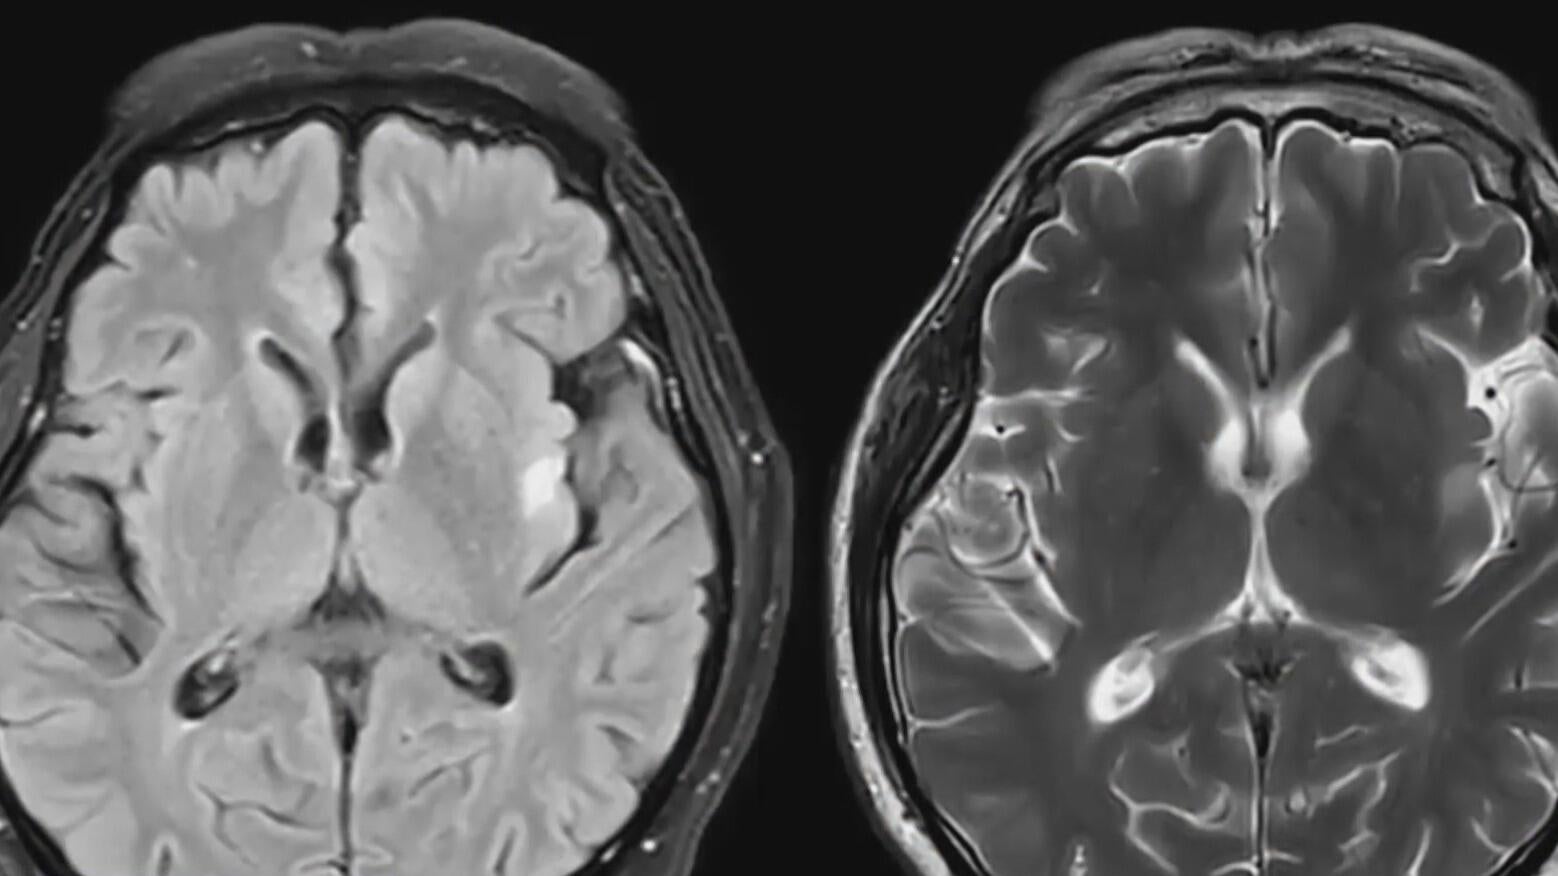

University of California, San Francisco researchers are studying the brains of more than 200 living former players for signs of chronic traumatic encephalopathy, also known as CTE, a degenerative brain disease that develops after repeated head injuries.

As of now, a diagnosis can only be made postmortem.

UCSF neurologist Dr. Gil Rabinovici and his team of researchers are aiming to develop reliable diagnostic tests while exploring factors that influence who develops CTE and why.